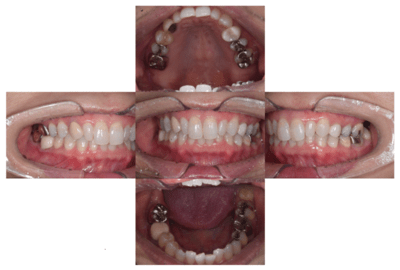

2022.7.9 経過観察後

口腔内写真

レントゲン写真

根管治療後3ヶ月です。根のまわりの骨がやや白くなってきているのがわかります。だんだん骨の添加がみられている証拠になります。

ここまで治癒していればかぶせ物をかぶせても問題ないと判断しました。

2022.8.13 クラウンセット

2022.10.16 予後経過

1年後 2023.3 予後経過

移植した歯はしっかり機能しており、問題なく使用できているとのことである。